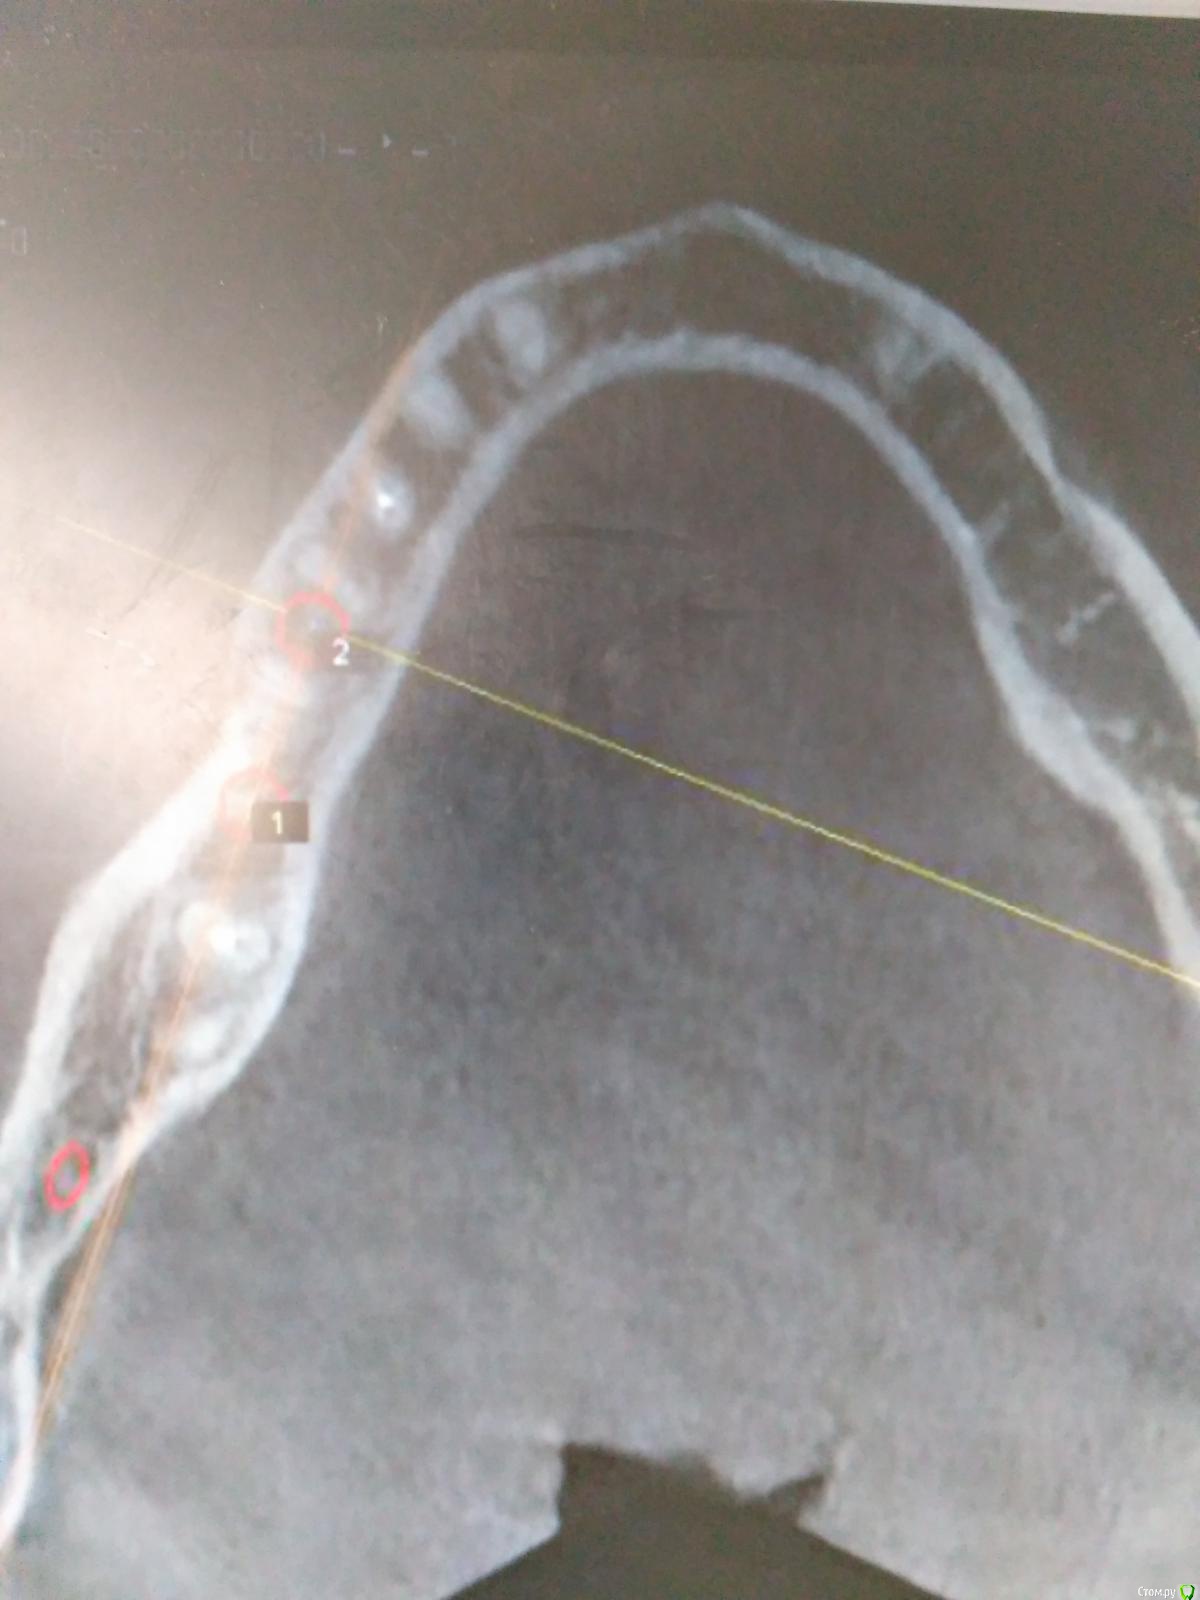

Пациент с жалобами на отсутствие 47 разрушение 46,48. После совещания с ортопедом и терапевтом принято решение удалять 46,48 и устанавливать импланты в позицию 46,47. post-48560-0-74269200-1490419709_thumb.jpgpost-48560-0-43642200-1490419772_thumb.jpgПрисутствует парадонтоз, лечение у пародонтолога прошел заранее. Решено было 46 ставить одномоментно, с графтом и мембранкой, 47 по стандартному протоколу, импланты alpha bio aic 4,2*12, 4,2*10 соответственно. post-48560-0-27512000-1490420040_thumb.jpgpost-48560-0-53003700-1490420066_thumb.jpg Сначала удалил, атравматично с распилом по бифуркации.post-48560-0-43340000-1490420143_thumb.jpgpost-48560-0-35881400-1490420170_thumb.jpgРаскрылся над 47, подготовил ложе, пины параллельности. Здесь вопрос, думаю зря широко отслоился и затронул 46?post-48560-0-32979400-1490420293_thumb.jpgpost-48560-0-94312700-1490420324_thumb.jpgустановка имплантов с фдм, графт в лунки 46 апатос, мембрана Эва. Снять не получилось. Нить моно 5-0. Тут опять вопрос фдм нужно было ставить шире? Но опять же импланты заглубил немного...post-48560-0-50977700-1490420493_thumb.jpg и контрольный. Конструктивная критика приветствуется)))

Фото надо обрезать. У Вас вестибулярный дефект одномоментно с графтом у 46 -лучше законсервировать лунку. 47 также дефицит тканей вестибулярно-сст на узкий фдм. Это какой-то новый альфабио? Я бы не оставлял такой формирователь на весь срок интеграции. На 47 ,судя по всему,фдм не сел,уступ мешает.